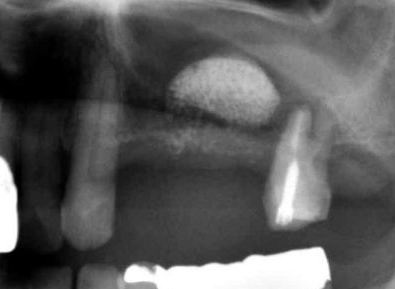

| B上顎洞底挙上術(サイナスリフト) | |||||||||||||||||||||||||||||||||||

| 上顎骨の内部には上顎洞と呼ばれる大きな空洞が存在します。 この空洞は様々な要因がきっかけとなり、拡大する傾向を持っています。 さらに、歯がなくなると歯槽骨も吸収しますので、上顎においては歯槽骨側と上顎洞側から骨吸収が進行することも少なくないのです。 そこで、膨らんできた上顎洞に移植骨や骨補填材、最近ではインプラント本体の一部を挿入して、 上顎洞の底部分を押し上げる技術があります。これが上顎洞底挙上術です。 もっと簡単なソケットリフト(インプラントを埋めるときに同時に人工骨などを填入して上顎洞を挙げる手術) もありますが、骨の厚みがかなり薄くて(1mm〜2mm)、ソケットリフトが出来ない場合に この上顎洞底挙上術(サイナスリフト)が行われます。 これが出来る技術を持っていることは、上顎に対してほとんどの症例でインプラントが可能になることを意味します。 |

| 側面の骨から、シュナイダー膜(上顎洞粘膜)を押し上げて人工骨を填入しました。 副作用もなく、順調に定着しました。 |